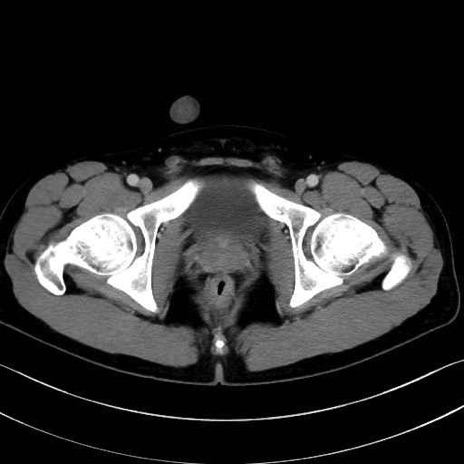

精嚢(seminal vesicle)のCT画像における解剖

症例

【症例】20歳代 男性 スクリーニング